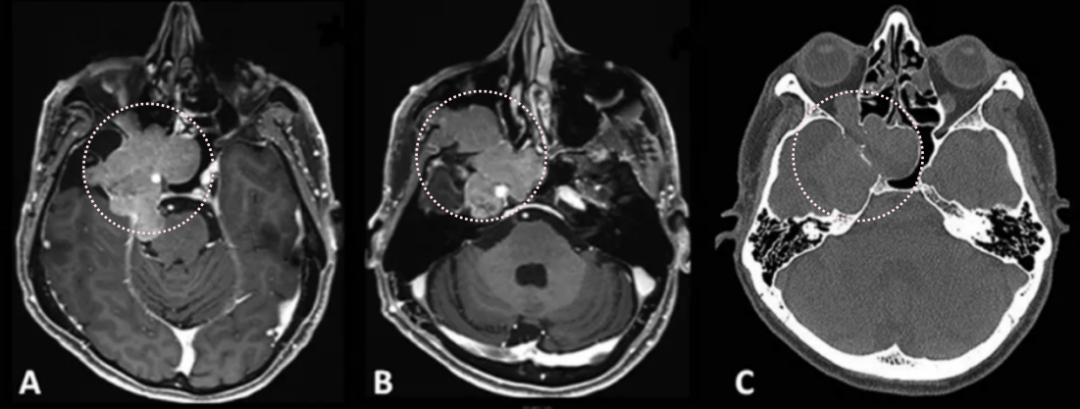

2012年,53岁的Leo突然发现自己嗅觉减退、视力下降时,就医检查发现右侧梅克尔腔脑膜瘤,随即进行了手术。谁能想到7年过后,脑膜瘤再次卷土重来,出现严重的V1(嗅神经)、V2(视神经)和V3(动眼神经)感觉减退和疼痛,症状比第一次手术前还要严重。磁共振成像(MRI)显示肿瘤大面积复发,延伸至海绵窦(CS)、后颅窝(PF)、蝶窦(SS)、翼腭窝(PPF)和颞下窝(ITF)。这个张牙舞爪的肿瘤,属实不太容易切除。

患者术前影像。(A)术前轴位T1加权钆增强磁共振成像(MRI),显示脑膜瘤延伸至后颅窝、海绵窦、眼眶和蝶窦。(B)肿瘤延伸至中颅窝、翼腭窝和颞下窝。(C)术前轴位计算机断层扫描(CT)显示蝶骨大翼侵蚀和蝶窦受累。